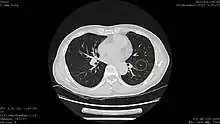

Calcified lung nodule seen on Low Dose Chest CT (circled)

Calcified lung nodule seen on Standard Dose Chest CT (circled)